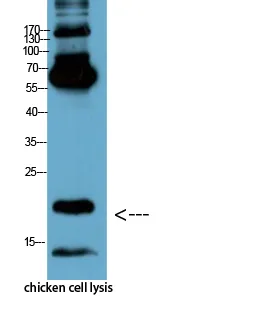

Active Caspase-3(5E1)Mouse Monoclonal Antibody

Cat: AMM06555

Size1:50μL Price1:$128

Size2:100μL Price2:$230

Size3:200μL Price3:$380

Application:IF-P,IF-F,ICC/IF,WB,IP,IHC-P

Reactivity:Human,Mouse,Rat,Chicken

Conjugate:Unconjugated

Optional conjugates: Biotin, FITC (free of charge). See other 26 conjugates.

Gene Name:CASP3

Size2:100μL Price2:$230

Size3:200μL Price3:$380

Application:IF-P,IF-F,ICC/IF,WB,IP,IHC-P

Reactivity:Human,Mouse,Rat,Chicken

Conjugate:Unconjugated

Optional conjugates: Biotin, FITC (free of charge). See other 26 conjugates.

Gene Name:CASP3